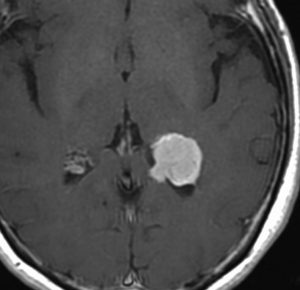

側脳室三角部髄膜腫 lateral ventricle (trigon) meningioma

50歳くらいの女性に偶然発見された三角部髄膜腫です。この部位はとても巨大にならないと症状が出ないので,しばらく様子を見ることにしました。

5年後です。増大傾向が止まりません。大きくなると手術リスクがすごく高くなるので,開頭手術で摘出することにしました。

右側は,手術翌日のMRIです。頭頂部の皮質経由で腫瘍は全摘出できています。専門的には,頭頂部経皮質到達法 parietal transcortical approach, high-parietal approachといいます。この患者さんは幸い頭頂葉症状は全く出ませんでした。でも巨大な三角部髄膜腫になると頭頂葉症候が手術後遺症として残ることがあります。でも慎重な手術をすれば日常生活に大きな支障となることはほとんどないでしょう。